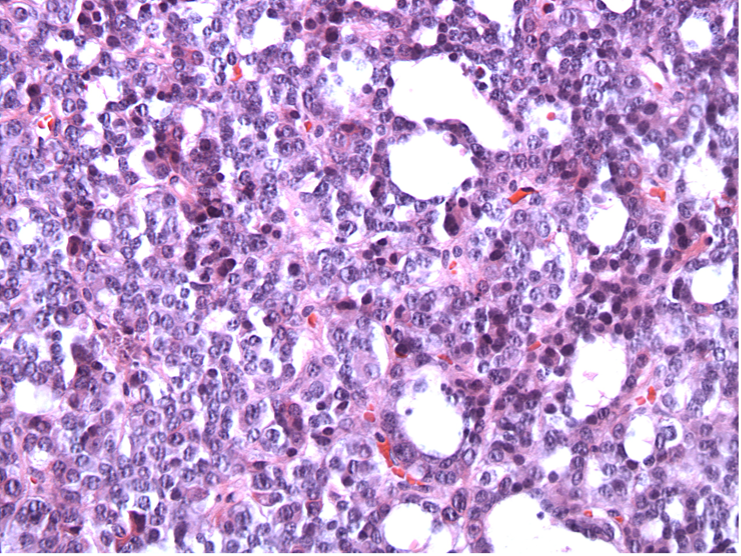

A 31 year-old man presented with enlarged supraorbital ridges, wide nose, and prognathism. Imaging studies demonstrate a thickened skull, enlarged frontal sinus, and a sella mass. Histopathology: solid neoplasm, interrupted by “pseudoglandular” spaces. Cells had eosinophilic cytoplasm and prominent nucleoli:

Discussion: Densely granulated somatotroph adenomas are eosinophilic and have a solid growth pattern. The pseudoglandular areas and prominent nucleoli are often seen in TSH adenomas. Pit-1 drives both GH and TSH (and Prolactin) producing adenomas. This patient had elevated TSH and GH on his lab studies. GH (left) and TSH (right) are below: